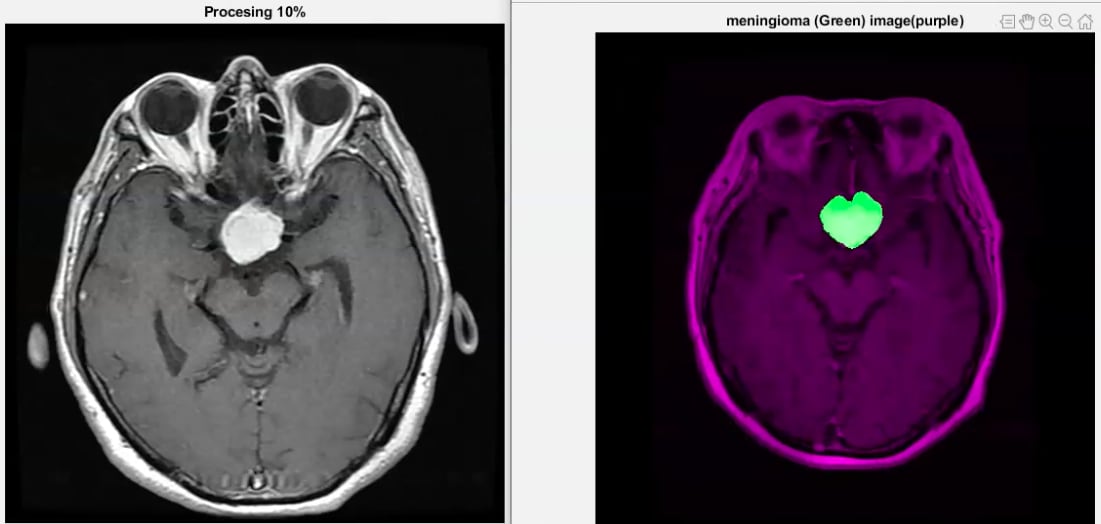

A finales del próximo mes de setiembre la empresa realizará el lanzamiento oficial de BrainTD, un software de procesamiento de imágenes médicas basado en inteligencia artificial, machine learning y deep learning.

Para que el sistema identifique un tumor se utilizan imágenes de cerebros sanos y de cerebros con diferentes tipos de cáncer.

Cuando se realiza un examen o tomografía computarizada, conocida como Tac, el sistema toma la imagen y la compara con el archivo para detectar tumores cerebrales en cuestión de segundos.

No es lo único que hace. Además, los clasifica según su tipo y segrega precisamente el área tumoral.

La segregación permite ahorrar tiempo clave para brindar la ubicación precisa del tumor y evitar errores humanos, exceso de estudios médicos posteriores, conocer el área precisa para el tratamiento y así evitar tomar una decisión tardía.